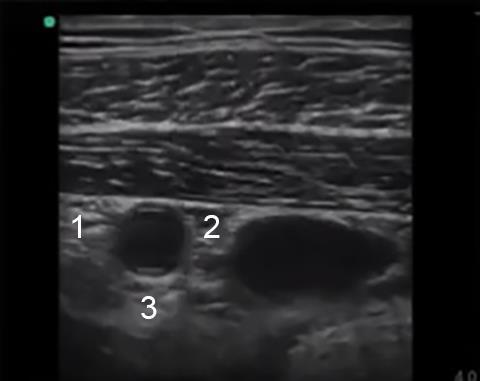

Bild: Infraklavikuläre Anatomie 2

Lateraler Strang

Medialer Strang

Posteriorer Strang